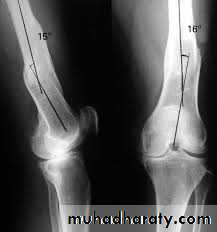

Deformities of the knee joint

In normal adult the knee are in 5-7 degree valgus ; any deviation from this may regarded as deformity .

The three common deformities are :

1- bow leg deformity (genu varum) .

2- knock knee (genu valgum) .

3- hyper extension(genu recurvatum) .

Measurement :

: distance between the femoral condyles with the legs held in full extension , and the heel touching ; it should be

less than 6 cm .

Knock knee

The distance between the medial malleoli when the knee are held touching; it is usually

less than 8 cm .